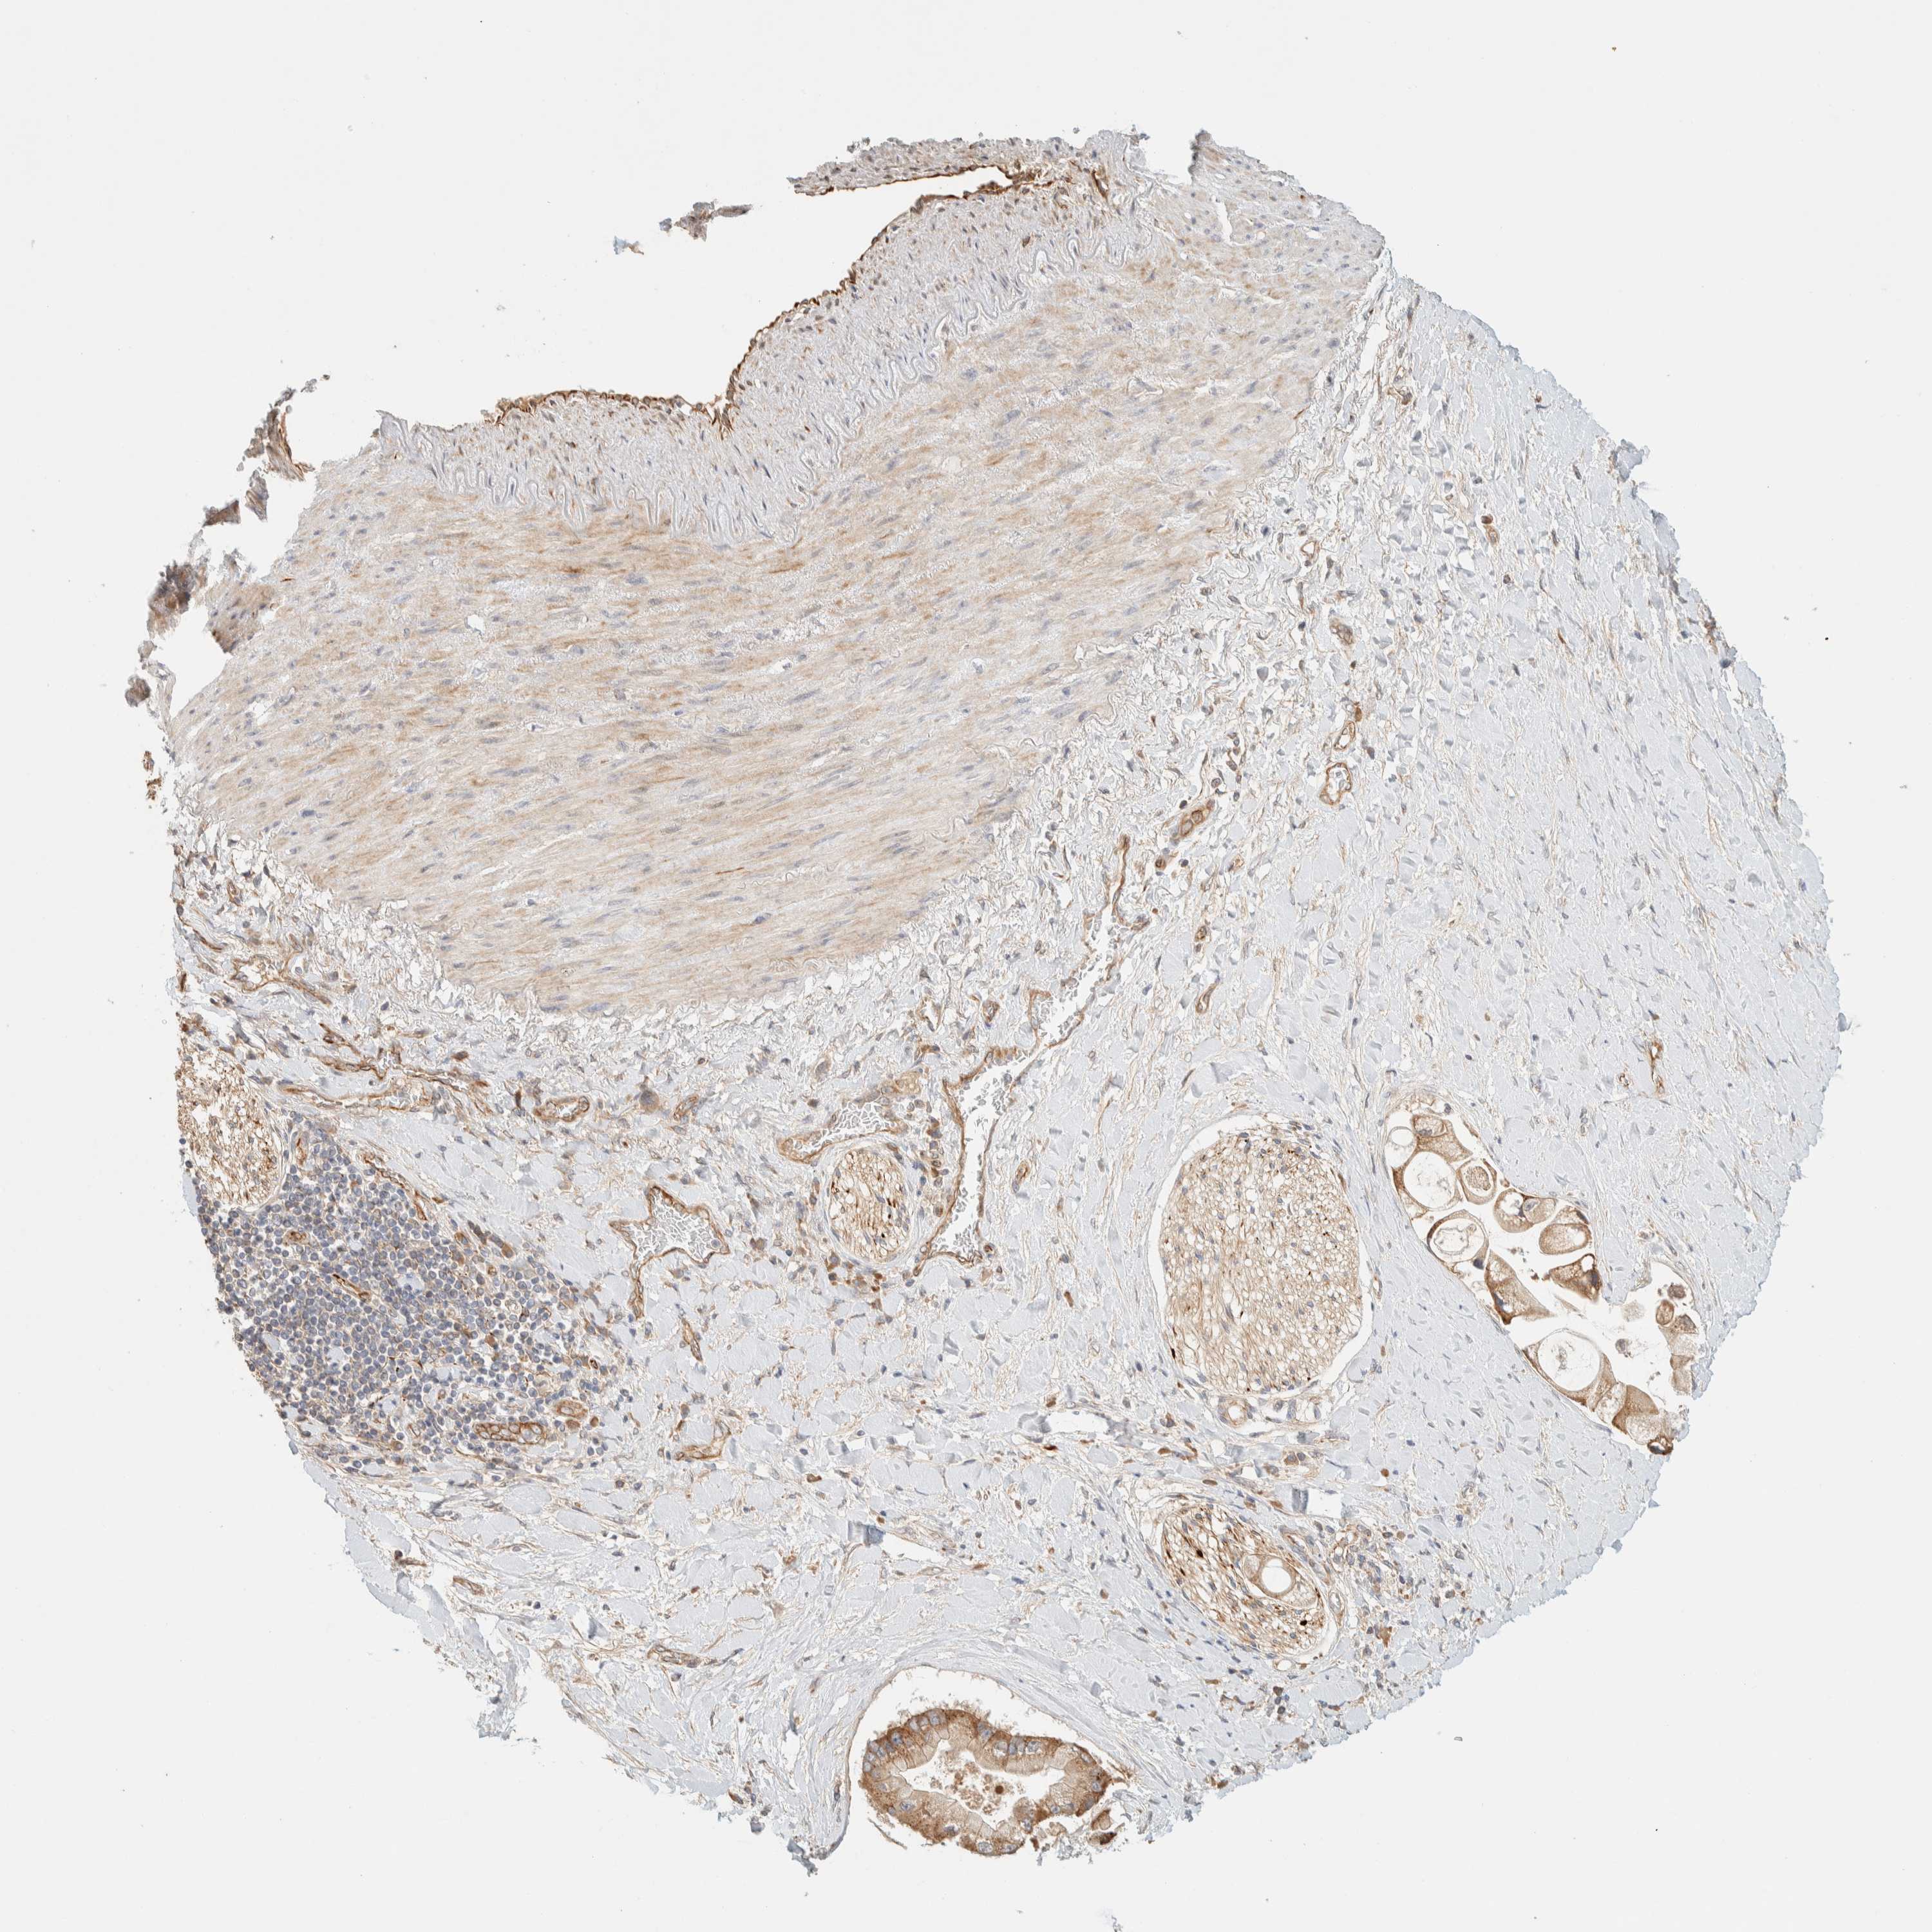

LIVER CANCER - Protein expressioni

A mouse-over function shows sample information and annotation data. Click on an image to view it in a full screen mode. Samples can be filtered based on level of antibody staining by selecting one or several of the following categories: high, medium, low and not detected. The assay and annotation is described here.

Note that samples used for immunohistochemistry by the Human Protein Atlas do not correspond to samples in the TCGA dataset.

Antibody stainingi

Antibody staining in the annotated cell types in the current human tissue is reported as not detected, low, medium, or high, based on conventional immunohistochemistry profiling in selected tissues. This score is based on the combination of the staining intensity and fraction of stained cells.

Each image is clickable and will lead to virtual microscopy that enables deeper exploration of all samples and also displays staining intensity scores, fraction scores and subcellular localization as well as patient and tissue information for each sample.

Antibody HPA001869

Antibody HPA023882

Staining

High

Medium

Low

Not detected

Intensity

Strong

Moderate

Weak

Negative

Quantity

>75%

75%-25%

<25%

None

Location

Nuclear

Cytoplasmic/membranous

Cytoplasmic/membranous,nuclear

Cholangiocarcinoma

Carcinoma, Hepatocellular, NOS